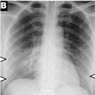

4.1. Data Processing

- GGOs.

- Odd paving pattern.

- Consolidation of the airspace.

- Thickening of bronchovascular bundles.

- Traction bronchiectasis.

- Reticular opacities.

- Vascular thickness.

- Additional widespread distribution along the bronchovascular bundles.

- Thickness in bronchial wall.